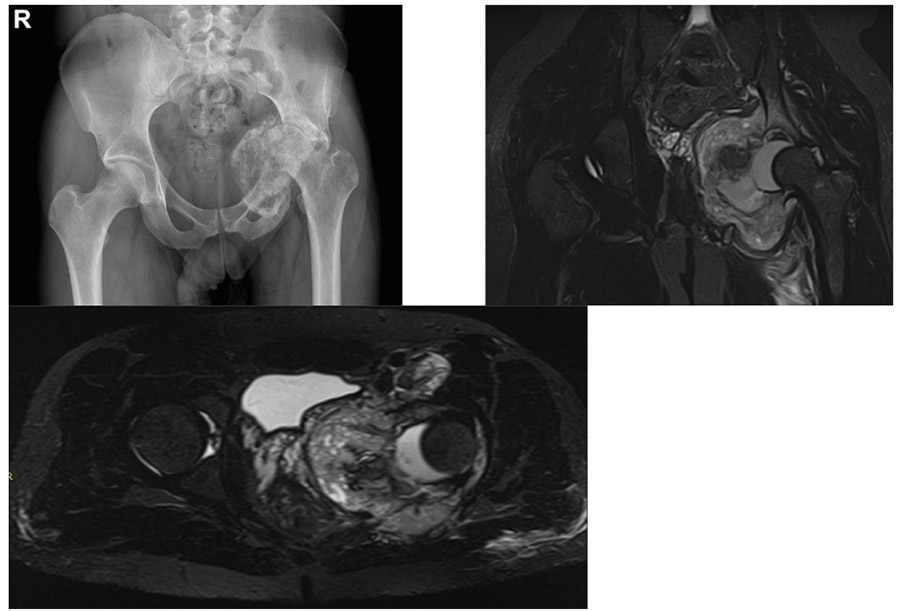

Before the surgery: The X-ray shows severe damage and a fractured dislocation in the left hip, and the MRI shows a large tumor tissue pressing on the pelvic organs.